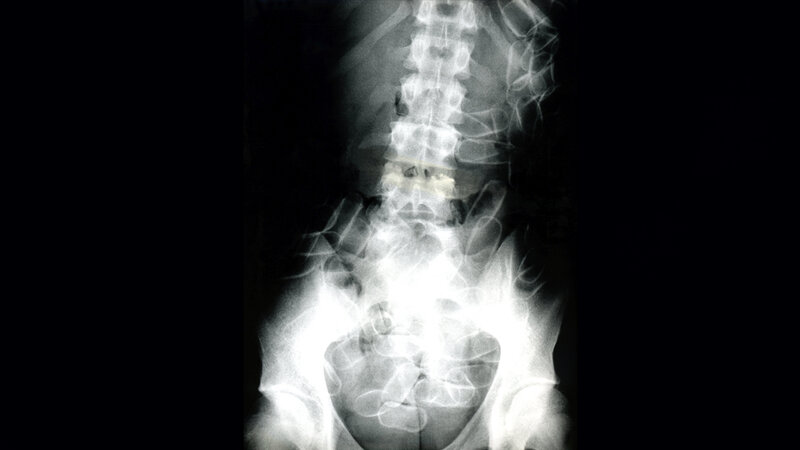

Die 27-jährige Südamerikanerin wollte von São Paulo/Brasilien über Frankfurt nach Minsk reisen und fiel in der Luftsicherheitskontrolle durch ihr nervöses Verhalten auf. Bei einer intensiven Nachkontrolle in einer Diskretionskabine fand die eingesetzte Luftsicherheitsassistentin im Slip der Brasilianerin fünf transparente Säckchen mit einem weißen Pulver. Gegenüber den hinzugezogenen Beamten der Bundespolizei gab die junge Frau zu, dass sie 67 Säckchen mit insgesamt etwa einem Kilogramm Kokain vaginal sowie oral aufgenommen habe.

Diese Menge entspricht einem geschätzten Straßenverkaufswert von etwa 60.000 Euro. Die Bundespolizei übergab die Brasilianerin zuständigkeitshalber an die Beamten des Zollfahndungsamtes Frankfurt am Main. Am 5. April wurde die Dame dem Haftrichter vorgeführt. Dieser verhängte Untersuchungshaft. Die oral aufgenommenen Behältnisse haben zwischenzeitlich unter ärztlicher Beobachtung auf natürlichem Wege den Körper der Drogenschmugglerin verlassen. (ots, red)